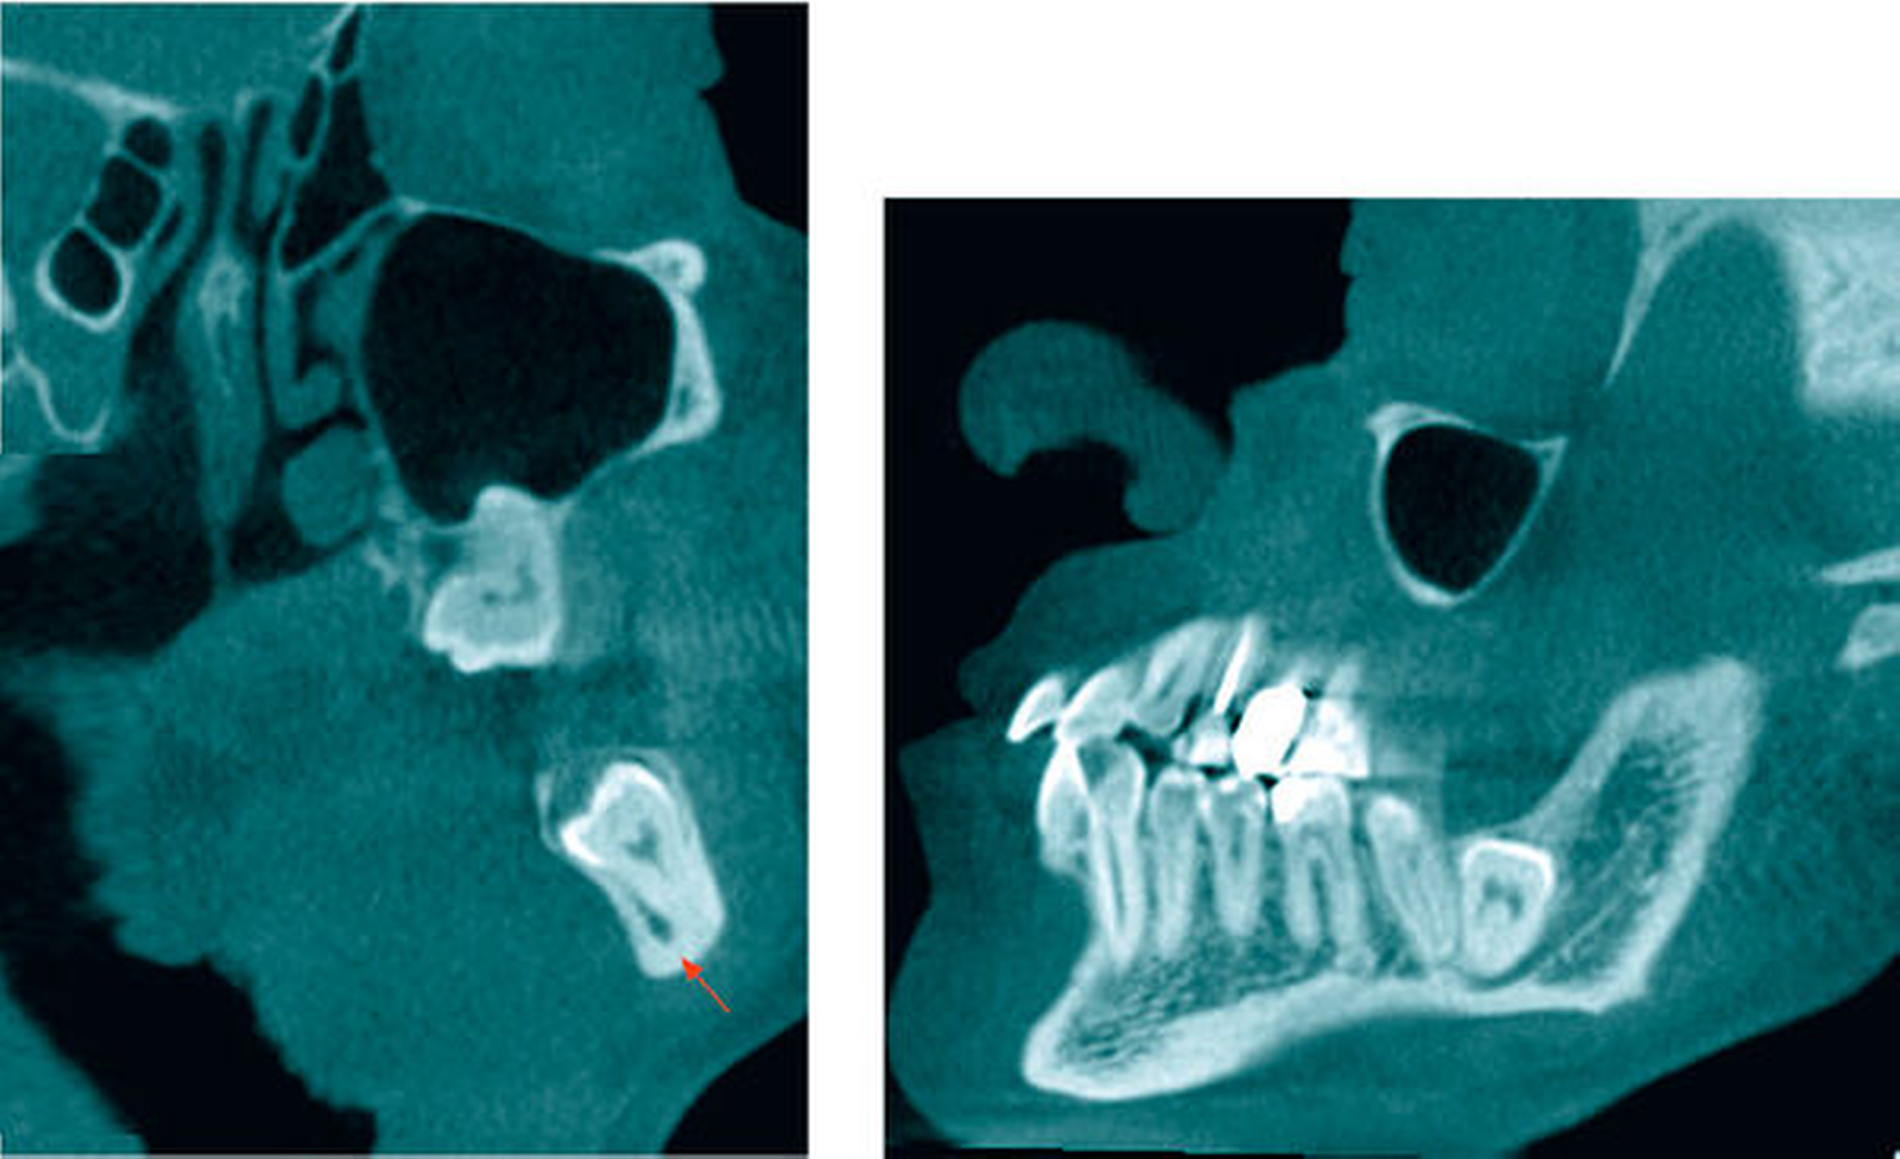

In der koronaren und der sagittalen Schicht des DVT zeigte sich deutlich die Lage beider Apices in der kaudalen Kompakta des Corpus mandibulae. Zudem wurde ein intraradikulärer Verlauf des Canalis mandibularis rechts durch die Wurzeln des 48 (Abbildung 2) erkannt. Am ebenfalls tief retinierten Zahn 38 konnte relativ zur Wurzel des Zahnes 38 ein lingualer Verlauf des Canalis mandibularis verifiziert werden (Abbildung 3).

Zur Abklärung der Lagebeziehung des 38 zum N. alveolaris inferior und relativ zum Unterkieferrand sowie zur Abklärung der Verlagerung des 28 beziehungsweise des Zustands der Kieferhöhle links wurde eine DVT durchgeführt. Dabei zeigte sich, dass der Nervkanal zwischen den vestibulär und lingual in der Unterkiefer-Kortikalis endenden Wurzeln des tief vertikal verlagerten Zahnes 38 verlief. Der Zahn 28 wurde mit Kronenbeginn kranial im apikalen Wurzeldrittel des Zahnes 27 vertikal verlagert dargestellt (Abbildung 7).